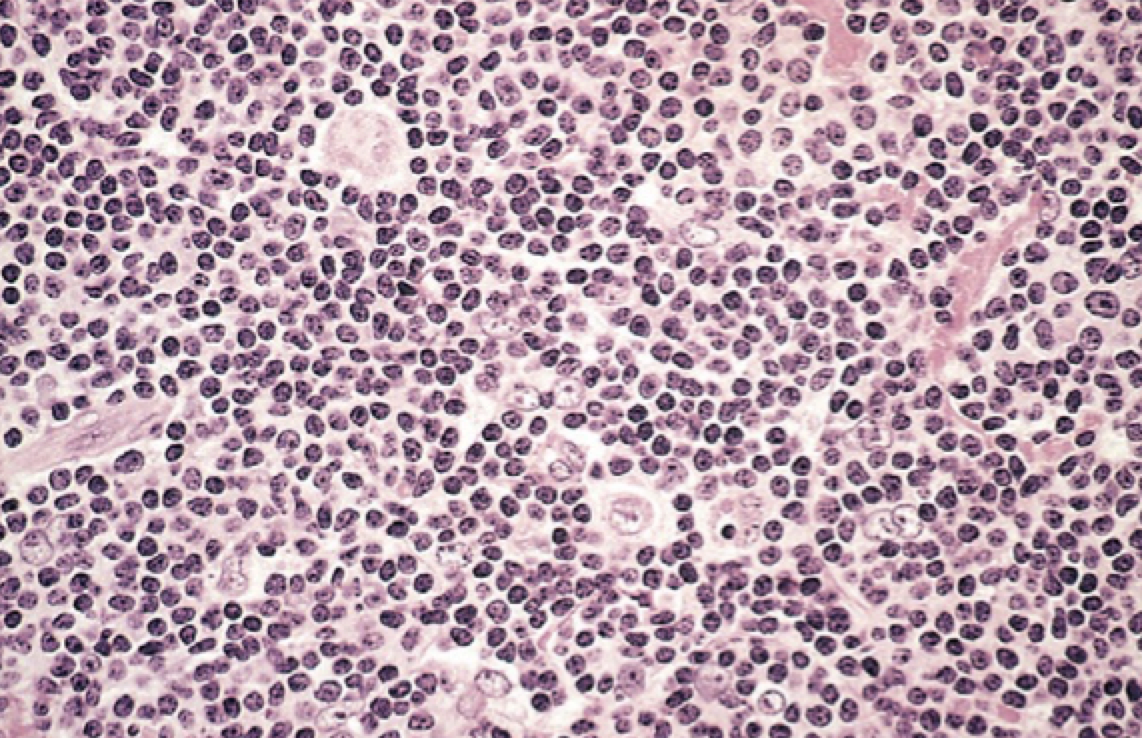

Микропрепараты: Лимфогранулематоз и Нодулярный Склероз

Раздел: Секреты мастерства